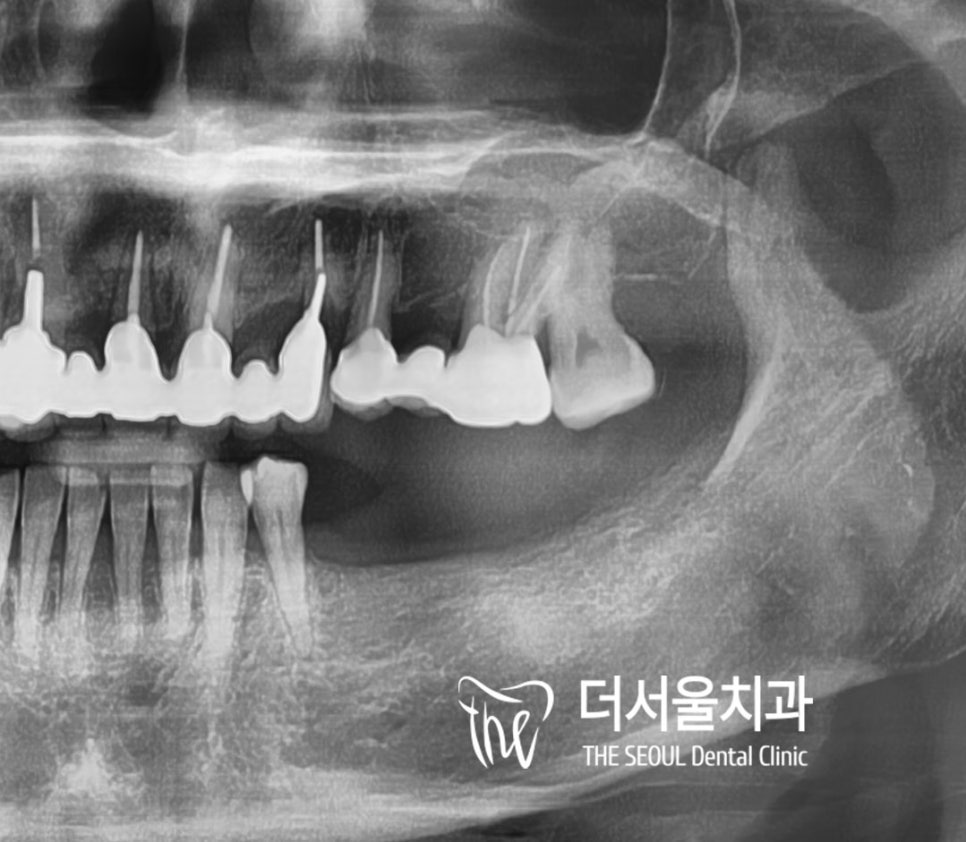

1. 초진

왼쪽 아래 치아가 없어

오른쪽으로 겨우 식사를 하시다가

이제는 턱관절에도 문제가 생겨

성남 수면마취 임플란트를 하러 오신 분입니다.

그런데 엑스레이를 보니

그간 다른 이들을 치료받은 흔적이 보이더군요.

2. 진단

우선 정확한 상태를 보기 위해

구강 내를 살펴봤는데

딱 봐도 왼쪽 아래 다수의 어금니가 없고

잇몸 뼈가 얇고 부족한 것이 느껴지시나요?

이 분은 브릿지 보철을 하기에도

지지대 역할을 할 맨 뒤 어금니가 없어서

성남 수면마취 임플란트를 하시는 게 베스트인데